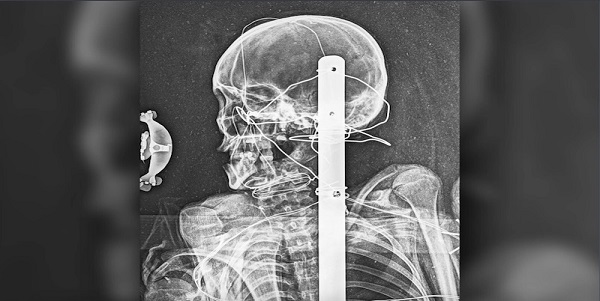

Fakat müze çalışanları nihayet bu ilgi çekici mumya hakkında biraz daha fazla bilgiye sahip olabildi. Mumya ilk kez bir X-ray tarayıcısıyla tarandıktan sonra, mumyalanan kişinin düşünülenden daha genç olduğu, yetişkin bir adamdan ziyade bir gence ait olduğu keşfedildi. Ve uzmanlar, iskeletindeki ipuçlarının, çocuğun ölümünden önce sağlık sorunları çekmiş olabileceğine işaret ettiğini söylüyor.

X-ışını bilgisayarlı tomografi(BT) taraması genellikle yumuşak dokuları incelemede kullanılır. Ancak mumya, 1950’lerden bu yana ahşap ve camdan yapılmış büyük bir vitrin kasası içinde tutuluyordu. Taşınması zor olan bu kasa BT tarayıcısı için çok büyüktü. Geisenger’den tıp direktörü Dr. Scott Sauerwine, bu yüzden geleneksel olarak mumyayı X-ışınından geçirmek ve kemiklerinden neler yapılabileceğini öğrenmek için Pensilvanya Danville’deki Geisinger Radyoloji merkezine dönüldüğünü söylüyor.

Mumyayı X ışınlarından geçirmek kolay olmadı. Büyük kasanın içindeki konumu, teknisyenlerin pelvis hakkında net bir görüş elde etmelerini önledi. Fakat kafatasının ve vücudun diğer kısımlarının iyi açılarını yakalayabildiler.

Sauerwine, “Bazı kemiklerde büyüme plakaları kaynaşmamıştı, bu kişinin onlu yaşlarının sonlarında olduğunu tahmin ediyoruz.” diyor.

Radyologlar mumyanın ayaklarını X ışınından geçirdiklerinde birkaç ayak parmağının eksik olduğunu not etti. Sauerwine, ampütasyonların (bir uzvun kesilmesi) binlerce yıldan beri yaşandığını ve gençlerin ayaklarını donma veya enfeksiyon nedeni ile kaybetmelerinin muhtemel olduğunu ve sonra yine, sert kullanım nedeniyle mumyalamadan sonra da ayak parmaklarının kopmuş olabileceğini söylüyor.

Kayıp parmaklar dışında vücutta travma veya iyileşmiş kırık belirtileri yoktu ve kemiklerde gencin ölümüne neyin sebep olmuş olabileceğine dair hiçbir net gösterge yoktu. Ancak radyologlar omurlarda anormal kalsiyum birikmeleri tespit ettiler.

Sauerwine, “Yaşlanmayla birlikte bunun gibi omurga anormallikleri görürüz, ancak bu kişi yaşlı değildi.” diyor. Bu özel durum dahilinde genç, muhtemelen psüdogut (bir tür eklem iltihabı) veya hipoparatiroidizm (paratroid hormonu üretiminin az olması) gibi metabolizma bozukluklarından muzdaripti.